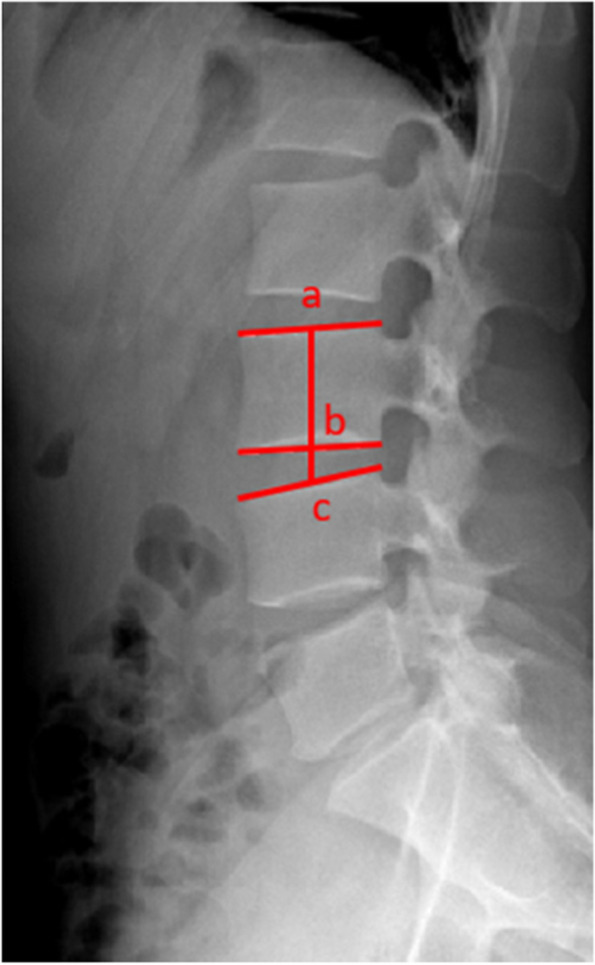

The radiological parameters included the preoperative and postoperative values of LL, pelvic incidence (PI), fixed-segment lordosis and range of motion (ROM), nonfusion segment and upper adjacent segment lordosis, disc height index (DHI) (Fig. 1), and modified Pfirrmann classification [14] of the discs.

Fig. 1.

Schematic diagram of the disc height index (DHI). The midpoints of the upper and lower endplates of the upper vertebral body are marked as a and b, respectively, and the midpoint of the upper endplate of the lower vertebral body is marked as c, DHI = bc/ab